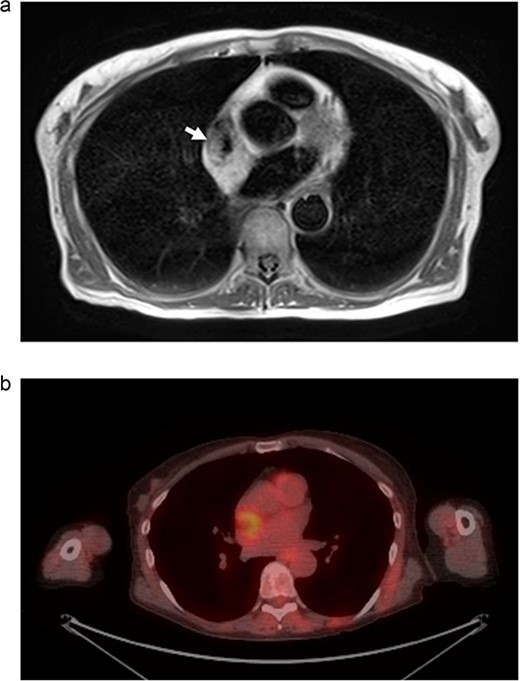

(a) Cardiac MRI. Mass is represented by the arrow on the right. The left arrow demonstrates the SVC. (b) PET/CT. Uptake is demonstrated in the right atrium. Uptake near the spine was determined to be artifact and not representative of metastatic disease.

We present another rare case of a hibernoma occurring just a few months later. A 63-year-old woman with history significant for HTN, COPD, GERD, ETOH abuse, and a 54-pack year tobacco use experienced continued weight loss of 70 lbs in the last 5 years. She underwent extensive workup for malignancy, which included MRI of the chest. MRI showed a 3.0 x 3.1 cm tumor circumferentially involving the superior vena cava at the atriocaval junction. This mass was hyperintense on T1 and T2-weighted images (Fig. 3a). Transesophageal echocardiogram was performed, and the mass was not appreciated. PET showed increased FDG uptake in the mass area without evidence of extracardiac disease (Fig. 3b). The recommendation was made for surgical resection.

(a) MRI chest. Mass represented by white arrow. (b) PET/CT. Uptake is demonstrated in the mass associated with the SVC and right atrium.